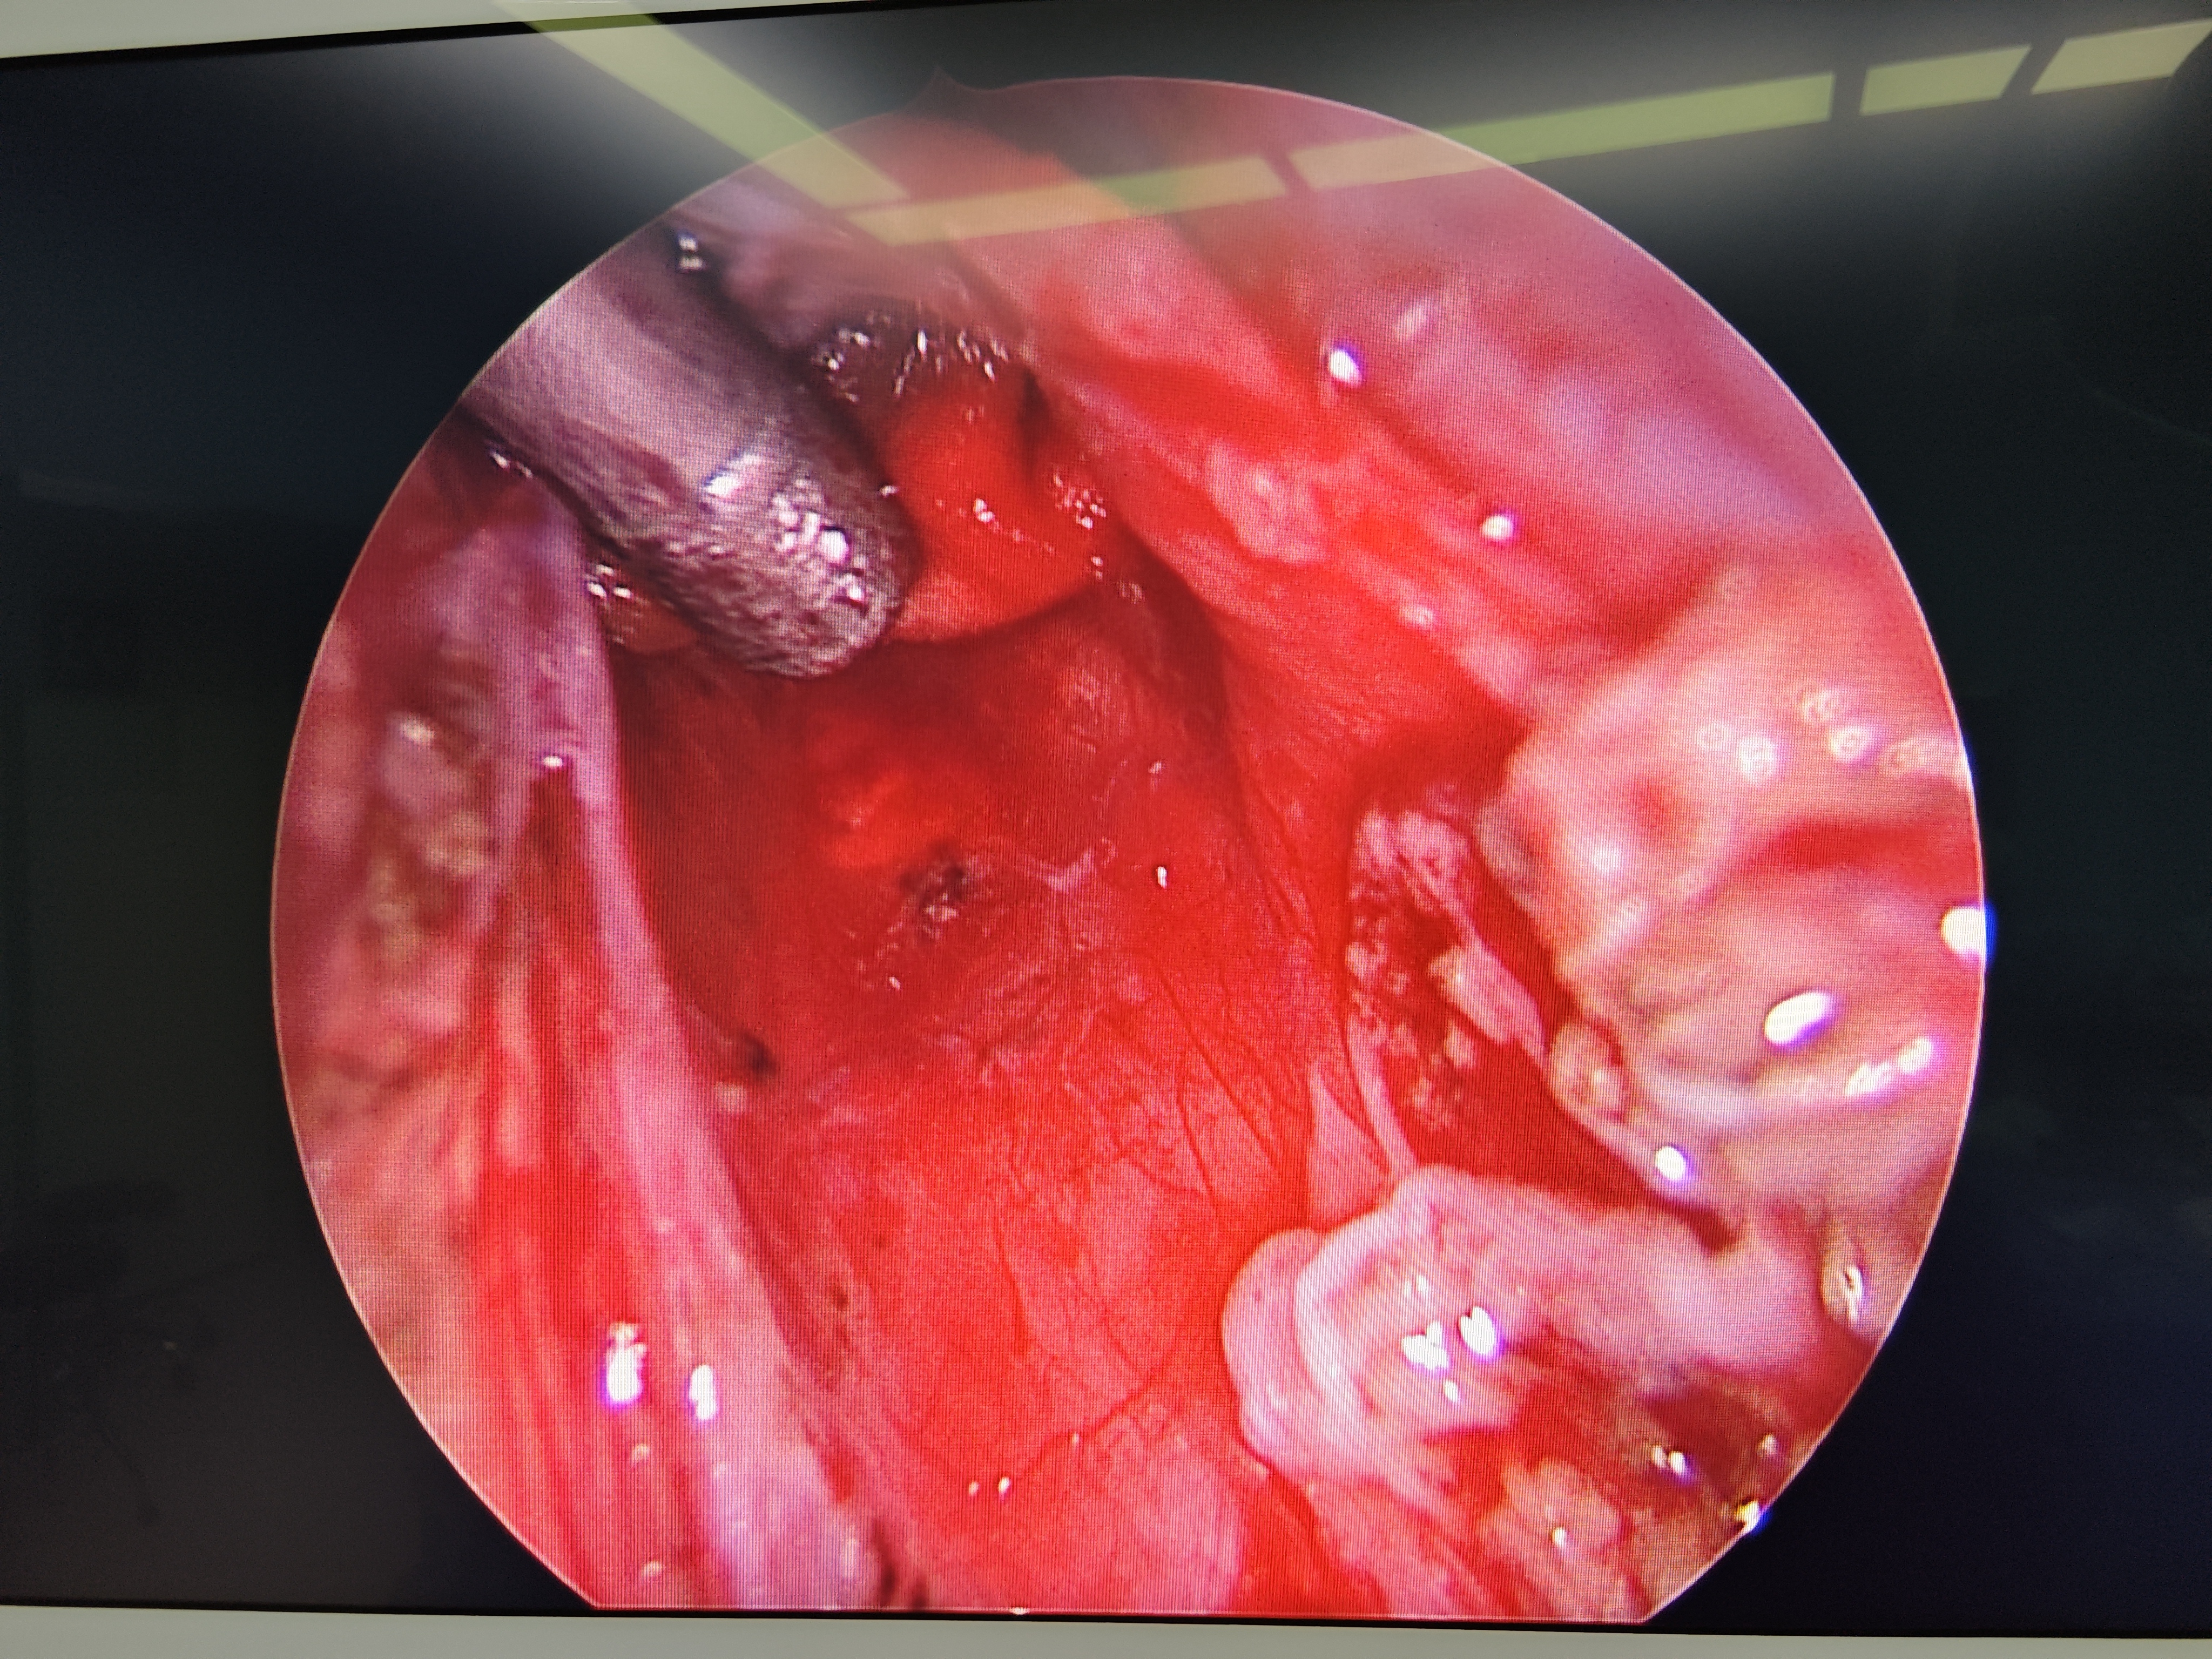

脊髓脊柱-脊髓脊柱肿瘤

神经纤维瘤病的治疗需要综合考虑患者的病情、症状、年龄、身体状况等因素,制定个性化的治疗方案。